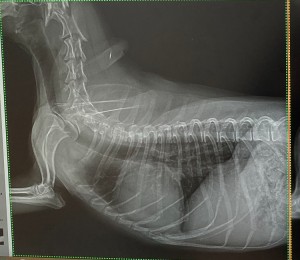

この度レントゲン機器を入れ替え、より鮮明な画像が描出できるようになりました。下の写真は同じワンちゃんのレントゲン写真です。旧機器で撮影したものが1枚目、新機器で撮影したものが2枚目です。

心臓、気管支、胸部の血管、骨の陰影、すべてにおいてより鮮明な画像になっていることが分かります。画質が向上することで診断精度は当然向上します。撮影にかかる時間も大幅に短縮(旧機器で1枚撮影するのに数分かかっていましたが、新機器は数秒)し、動物の負担も格段に減らすことができるようになりました。